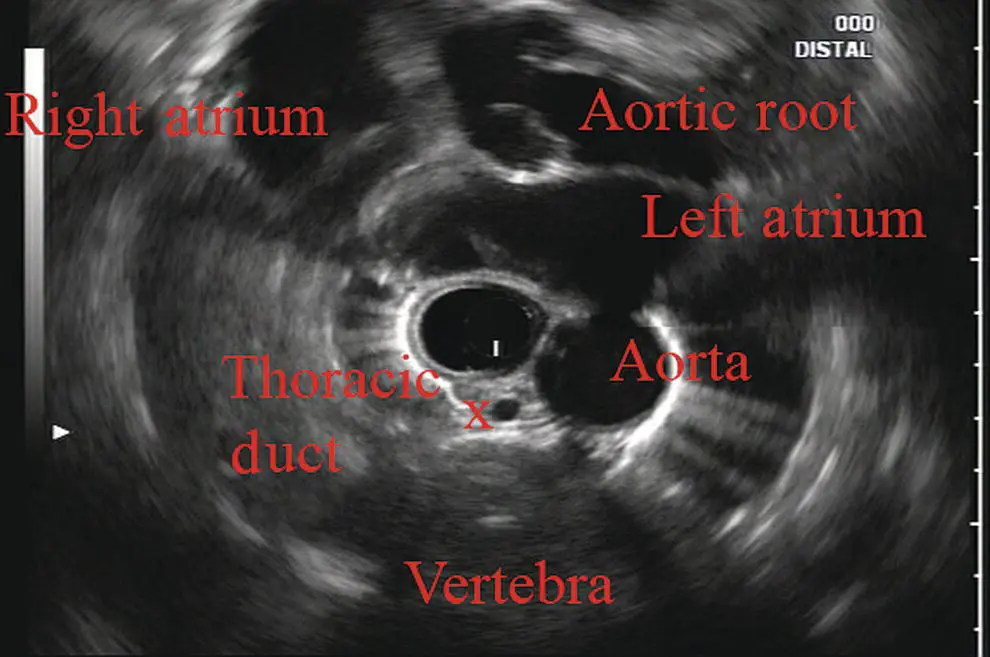

Further withdrawal upward to usually around 30–35 cm reveals the anechoic chamber of the left atrium in the 12 o’clock position ( Figure 2.3). With this field, relatively slight movement of the scope will reveal the mitral valve ( Figure 2.4), aortic root, and the aortic valve ( Figure 2.5). In the inferior portion of the field the descending aorta, the spine, the thoracic duct, and a relatively prominent azygos vein can be seen.

Figure 2.3 Radial array image at the level of the left atrium. PV, pulmonary vein.

Figure 2.4 Radial array image at the level of the mitral valve.

Figure 2.5 Radial array image at the level of the aortic root.